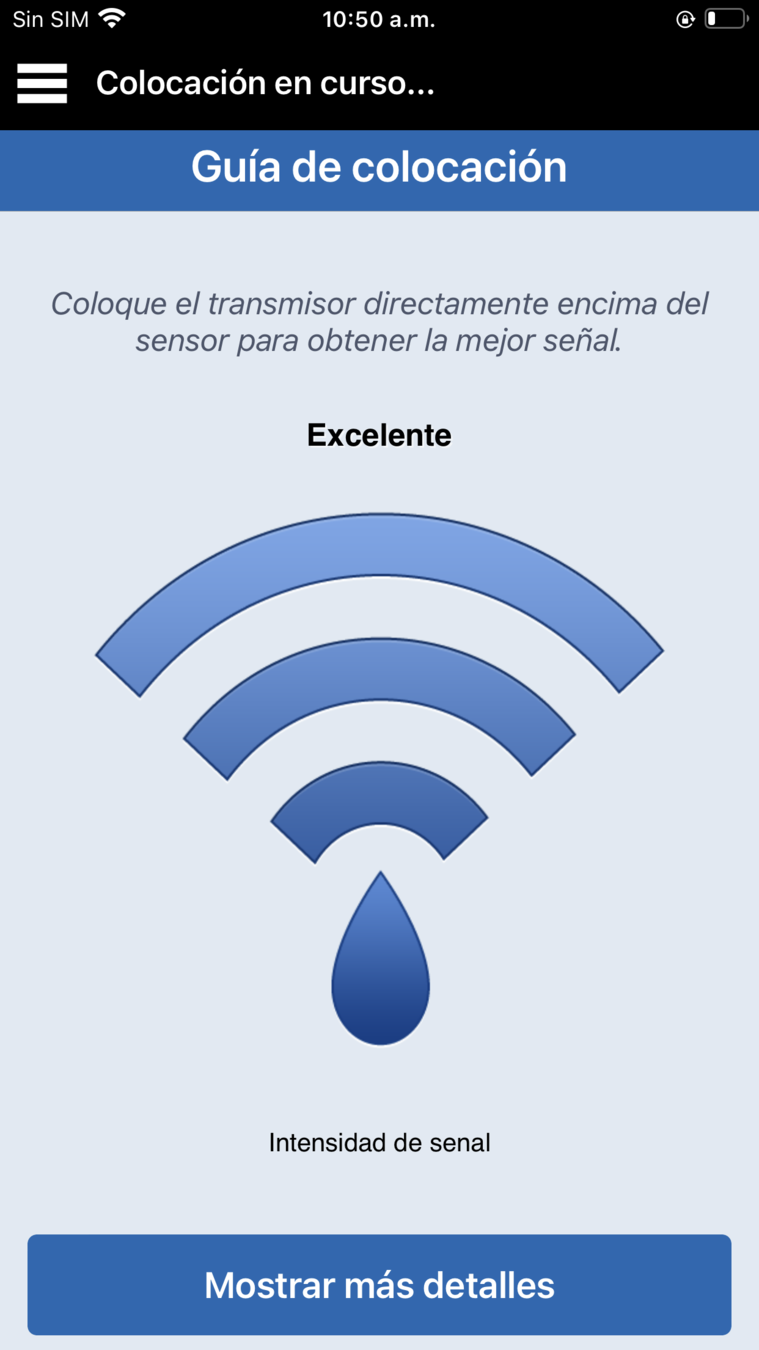

A continuación, abra la guía de colocación en la aplicación yendo al menú principal >

Guía de colocación.

A continuación, abra la guía de colocación en la aplicación yendo al menú principal >

Verá una X negra al principio.

Levante con suavidad y mueva ligeramente el transmisor inteligente junto con el adhesivo para encontrar la ubicación con la señal más fuerte, algún punto entre las 2-3 barras o de buena a excelente.

Puede ser de ayuda girar ligeramente el transmisor inteligente.

Cuando mueva el transmisor, deje que pasen unos segundos para que se actualice la señal antes de volver a moverlo.